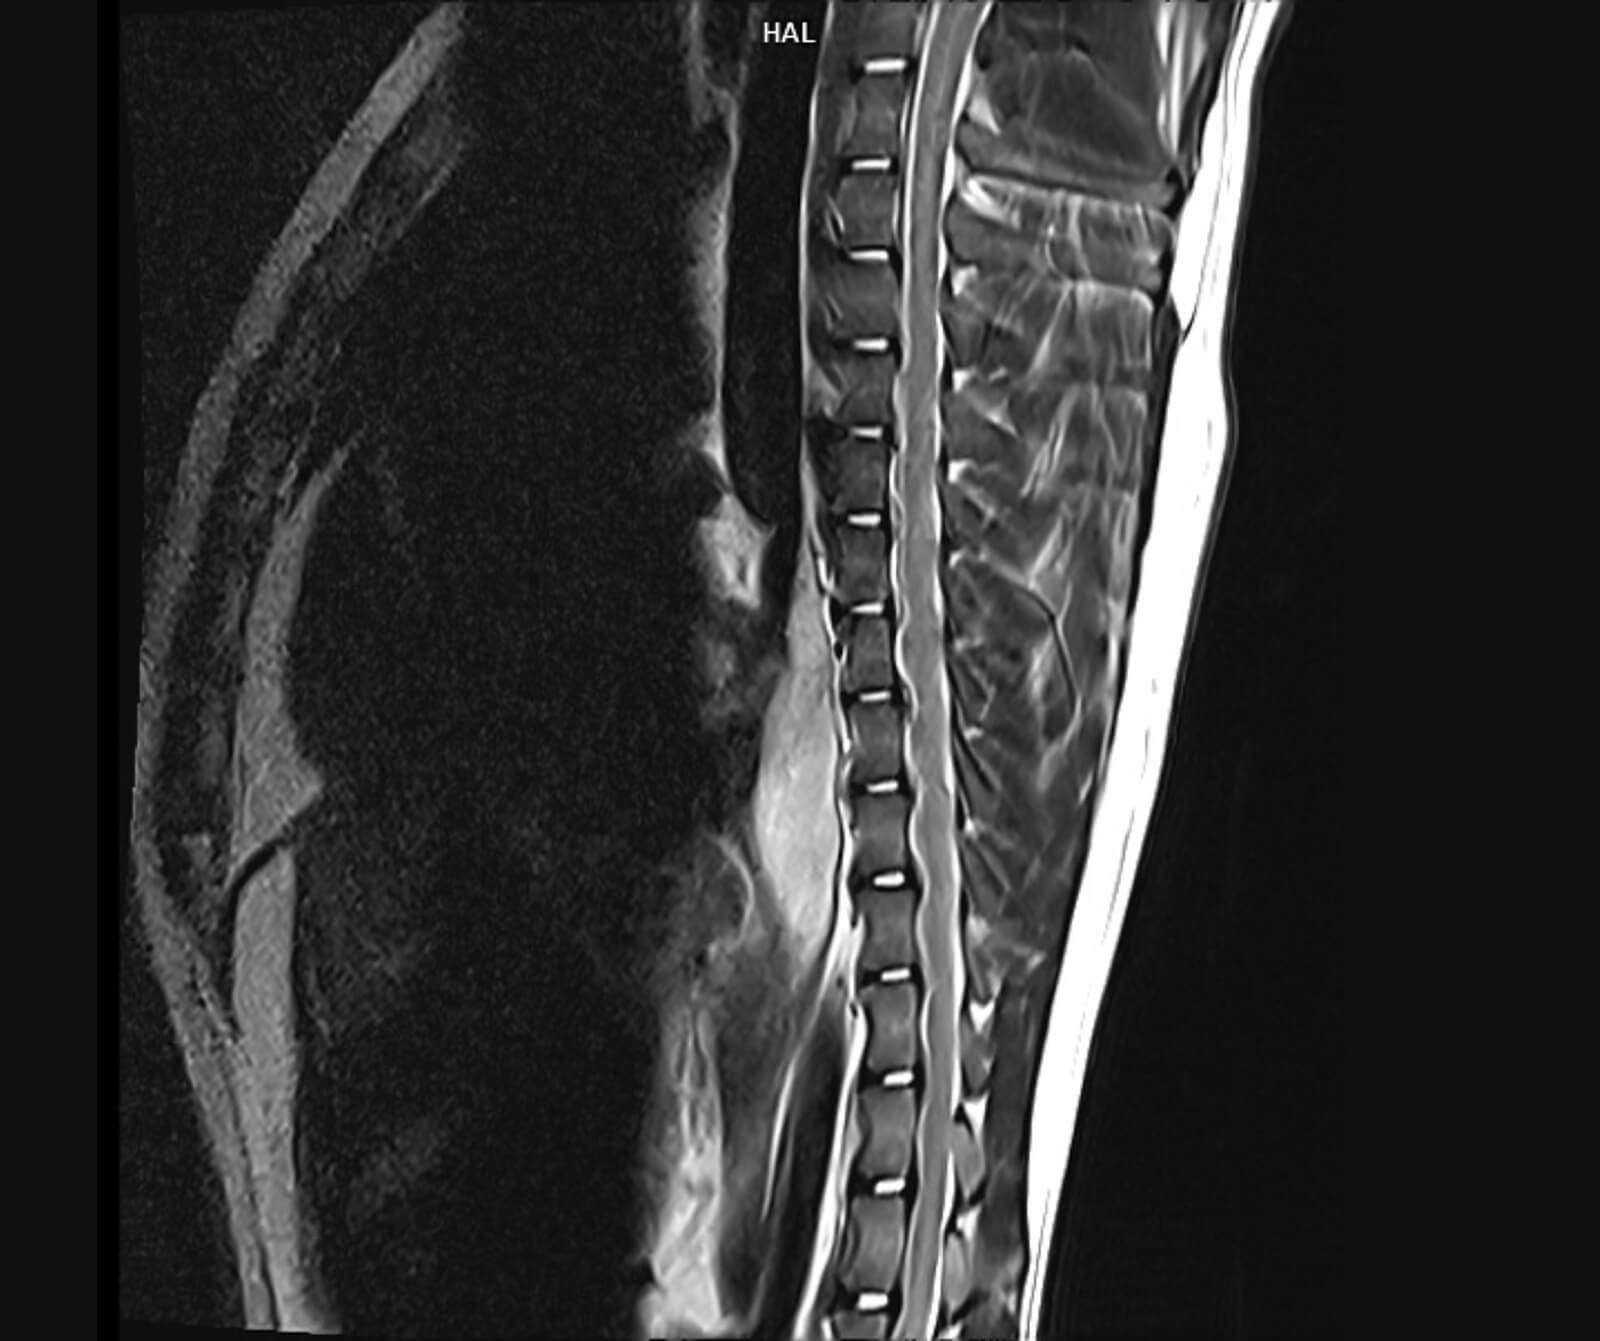

Veteriner hekimliğinde MR; beyin, omurilik, sinir sistemi, kas-iskelet sistemi ve iç organ hastalıklarının değerlendirilmesinde kritik rol oynar. Kemik yapılar dâhil olmak üzere vücudun tüm bölgeleri MR ile ayrıntılı şekilde incelenebilir.

• Spinal kord incelemeleri

• Disk hernisi, omurga tümörleri, enfeksiyonlar ve spinal stenoz

• Omurilikte travmatik ve dejeneratif değişiklikler